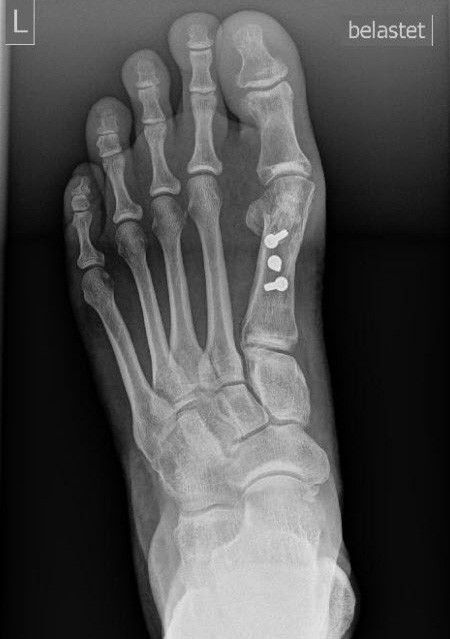

Die Untersuchung bestätigte eine typische, mittelgradige Hallux valgus Fehlstellung. Zusätzlich jedoch auch durch Druck auslösbare Schmerzen am Fussballen, genau unter dem Grundgelenk der zweiten Zehe. Die Stellung derselben war unauffällig, ebenso wie die Beweglichkeit. Die Röntgenbilder zeigten neben der Hallux valgus-Fehlstellung eine höchstens leichte relative Überlänge des zweiten Mittelfussknochens.

Bei entsprechendem Leidensdruck wurde eine operative Versorgung des Hallux valgus geplant, sowie die Verkürzung des zweiten Mittelfussknochens, um die dort bestehende Überlastung zu reduzieren. Einige Wochen vor dem geplanten Eingriff stellte sich die Patientin erneut vor, da sich innerhalb weniger Tage die Stellung der zweiten Zehe dramatisch verändert hatte, begleitet von deutlicher Schmerzzunahme.

Der geplante Eingriff wurde um die Reparatur der plantaren Platte erweitert und konnte 2 Wochen später durchgeführt werden. Die direkte Reparatur der plantaren Platte stellte lange ein technisches Problem dar, da sie unter den Gelenken in der belasteten Zone des Fussballens gelegen ist. Narben in diesem Bereich werden nicht gut vertragen und führen oft zu lang andauernden Beschwerden. Mittlerweile ist die direkte Reparatur von oben möglich, indem man die Platte durch die Grundgelenke hindurch erreicht. 4 Wochen nach der Operation konnte die Patientin vom Vorfussentlastungsschuh auf normales Konfektionsschuhwerk wechseln. Ein Jahr nach dem Eingriff läuft die Patientin schmerzfrei, die Stellung der Zehen blieb seither unverändert.